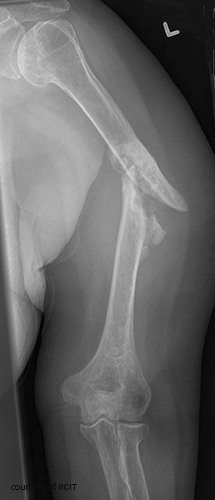

What nerve is at risk in humeral shaft fractures?

Radial nerve.

What type of forces cause different humeral fracture patterns?

Torsion = spiral, transverse = angled blow, high energy = comminuted.